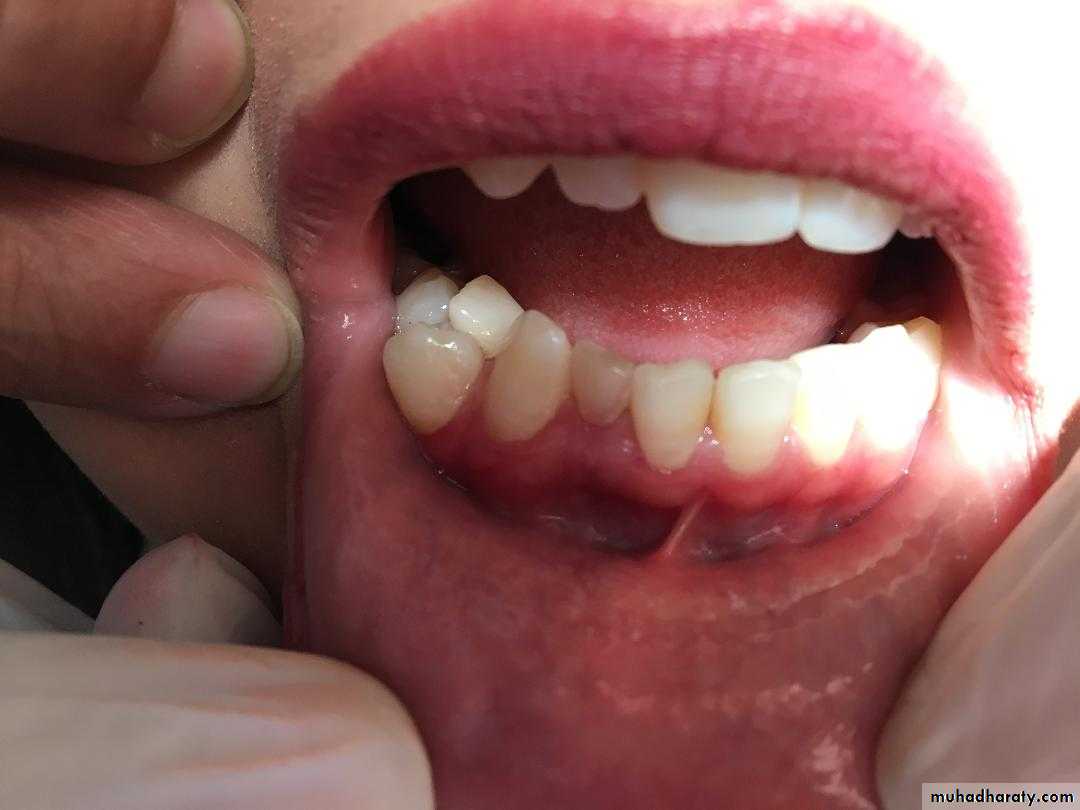

Paramolar blocking the eruption of 3rd molar.

Gemination (twining):

*Gemination is a rare anomaly that arises when the tooth bud of a single tooth attempts to divide.

The result may be an invagination of the crown, with

partial division, or in rare cases complete division

throughout the crown and root, producing identical

structures. Complete twinning results in a normal tooth

plus a supernumerary tooth in the arch.

CAUSE: is unknown, or it may be familial.

*The patient has a larger tooth but a normal number of teeth overall, in contrast to fusion, where the patient would appear to be missing one tooth.

MANAGEMENT : Affected teeth can cause malocclusion and lead to periodontal disease.

the affected tooth may be removed (if it is deciduous).

the crown(s) may be restored or reshaped.

OR the tooth may be left untreated and periodically examined to preclude the development of complications.

• Fusion of the left mandibular central and lateral incisors (twoindividual roots, two root canals and two joined crowns).

Gemination of right mandibular central incisor has one root, one root canal and a partially bifid dental crown.